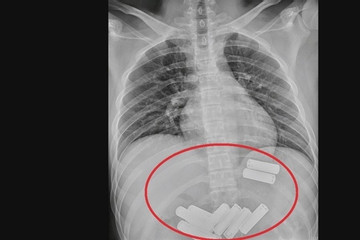

Cái kết đắng cho người đàn ông cố tình nuốt 11 viên pin vào bụng

TRUNG QUỐC - Người đàn ông đã phải trải qua gần một tiếng đồng hồ nội soi đau đớn để lấy dị vật ra ngoài.